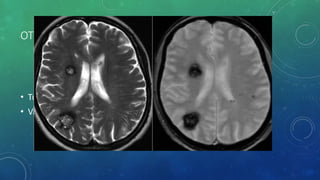

OTHER CAUSES -

• Tumors- contrast

• Vascular malformations – cavernoma – Hemosiderin - GRE